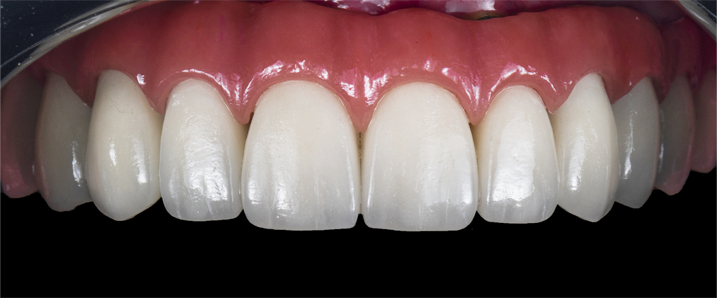

특별한 심미치료

치아 디자인의 완성, 심미보철